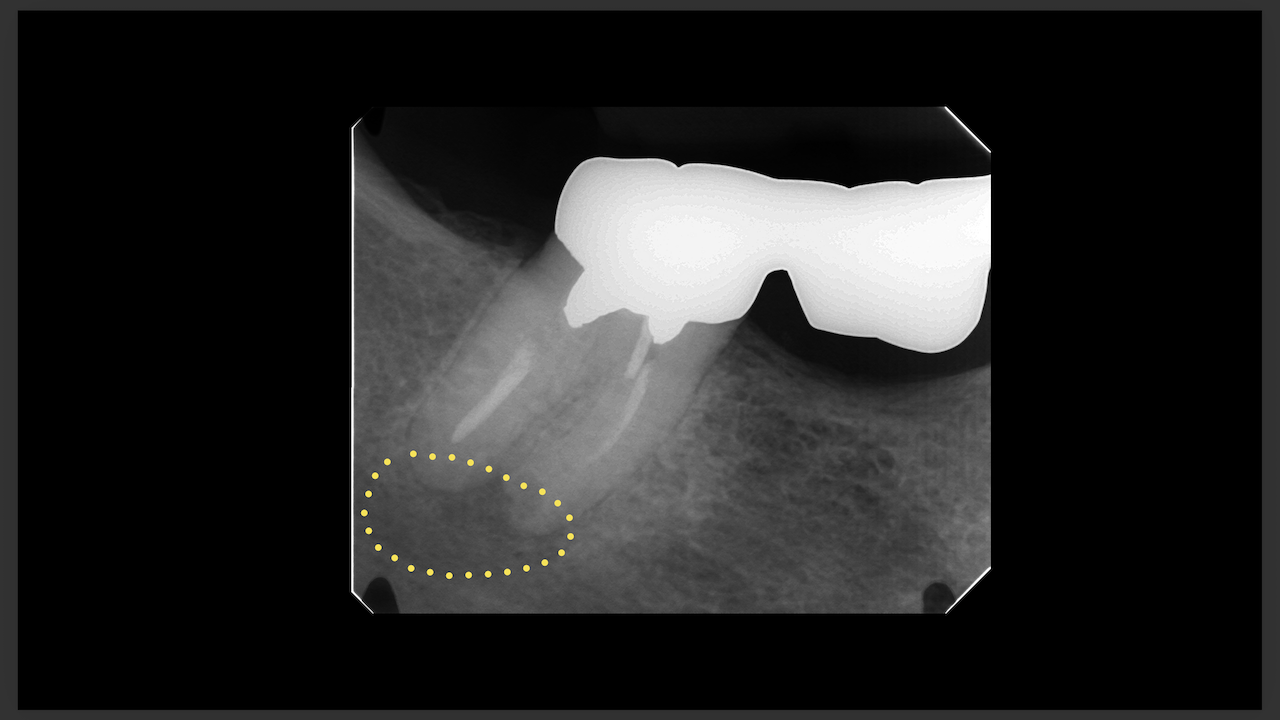

次が勤務医の立場でこのコースに来られたA先生。

エンド-ペリオ病変を有する歯の根管治療を発表していただいた。

ここから3ヶ月が経過した。